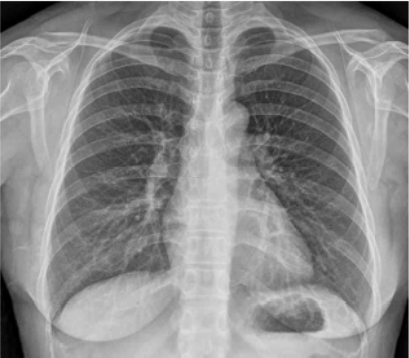

32세 여자가 2년 전부터 가끔씩 숨이 차고 기침을 한다며 병원에 왔다. 숨이 찰 때에는 휘파람 소리가 가슴에서 들린 적도 있다. 감기를 앓고 나면 잔기침만 한 달 넘게 가곤 했다. 기침으로 새벽에 잠을 깬 적도 있다. 5년 전부터 콧물과 코막힘이 자주 있다고 한다. 호흡음은 정상으로 들린다. 가슴 X선사진이다. 우선 시행할 검사는?

CXR: No remarkable findings